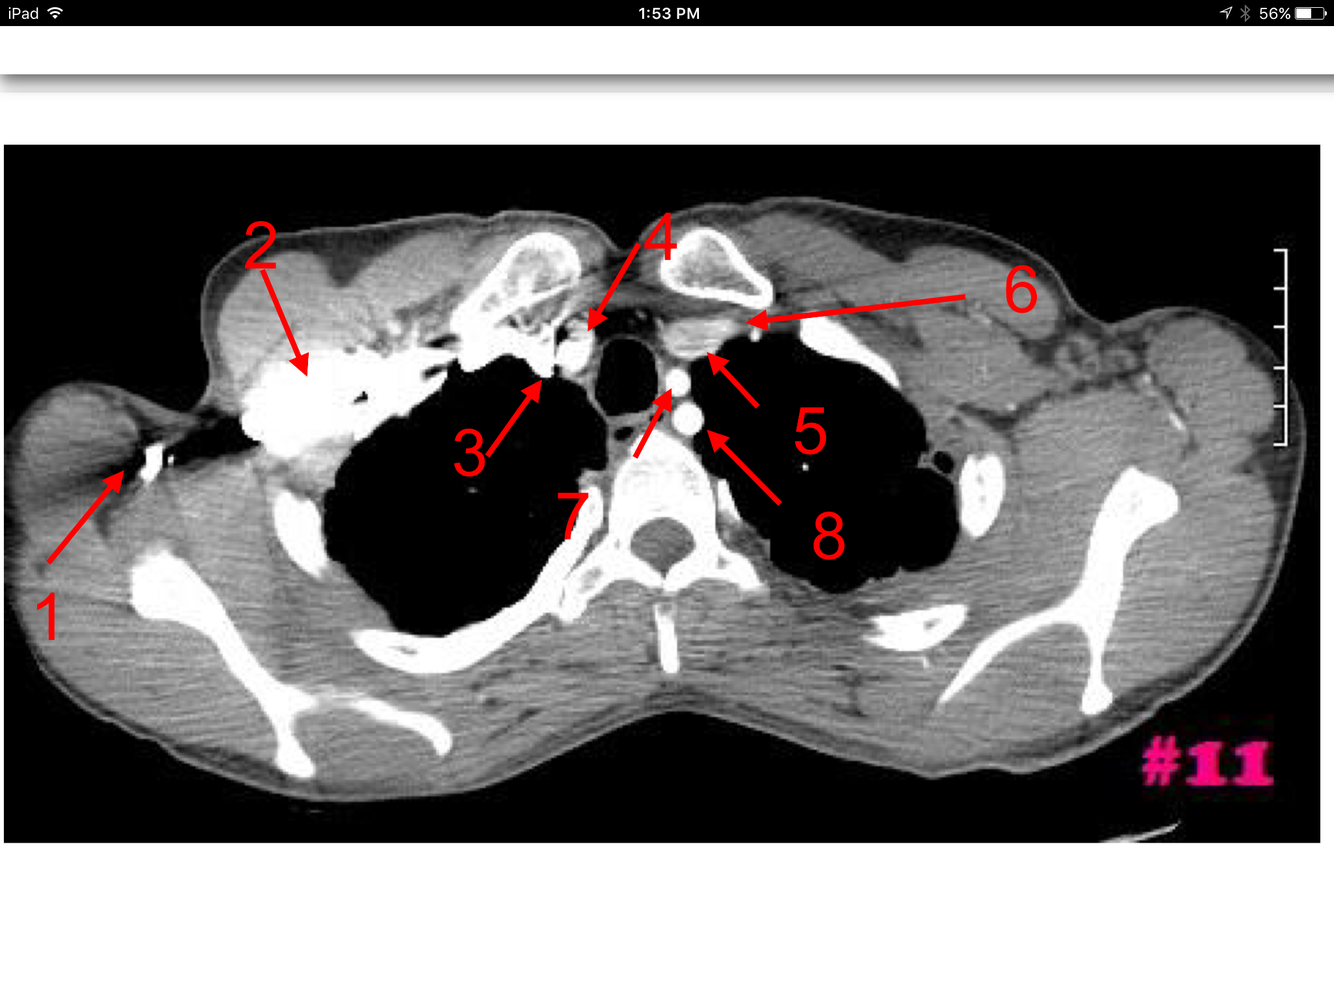

11

Q

A

Rt and Lt common carotid arteries

Rt and Lt internal jugular veins

Rt and Lt lobes of the thyroid gland

Rt and Lt vertebral arteries

How well did you know this?